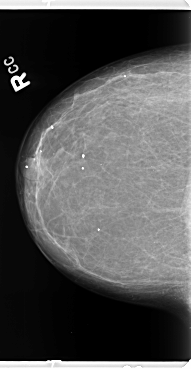

B_3099_1.RIGHT_CC

RIGHT_CC LINES 4792 PIXELS_PER_LINE 2472 BITS_PER_PIXEL 12 RESOLUTION 50 NON_OVERLAY